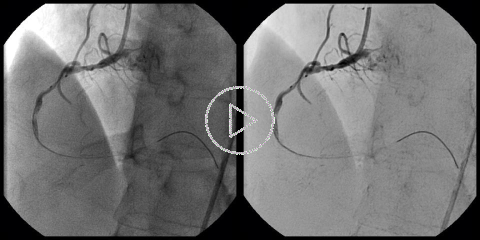

Locally Optimized Windowing (LOW):

Locally Optimized Windowing (LOW) provides a single frame image contrast enhancement performed by applying "windowing" of the pixel intensity values, not globally, as is usually done, but locally based on the locally computed envelopes of the original values.